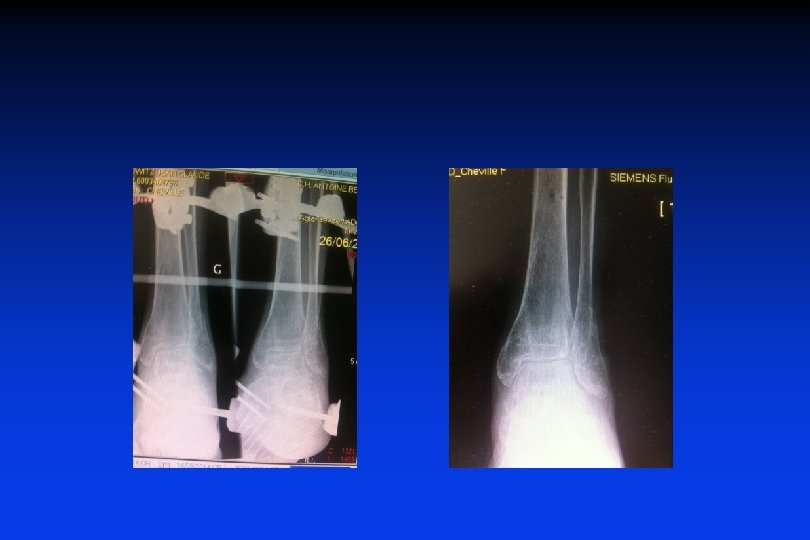

Traitement des fractures malléolaires Fractures déplacées : Ostéosynthèse à tout âge avec immobilisation postopératoire systematique

Fracture bimalléolaire + marginale postérieure Ostéosynthèse par simples vis

Toujours face et profil +++ règle fondamentale ++++

Fracture en Abduction sus-ligamentaire Ostéosynthèse de la fibula par plaque Réduction du diastasis T-F inf par 1 vis + Suture du LCM